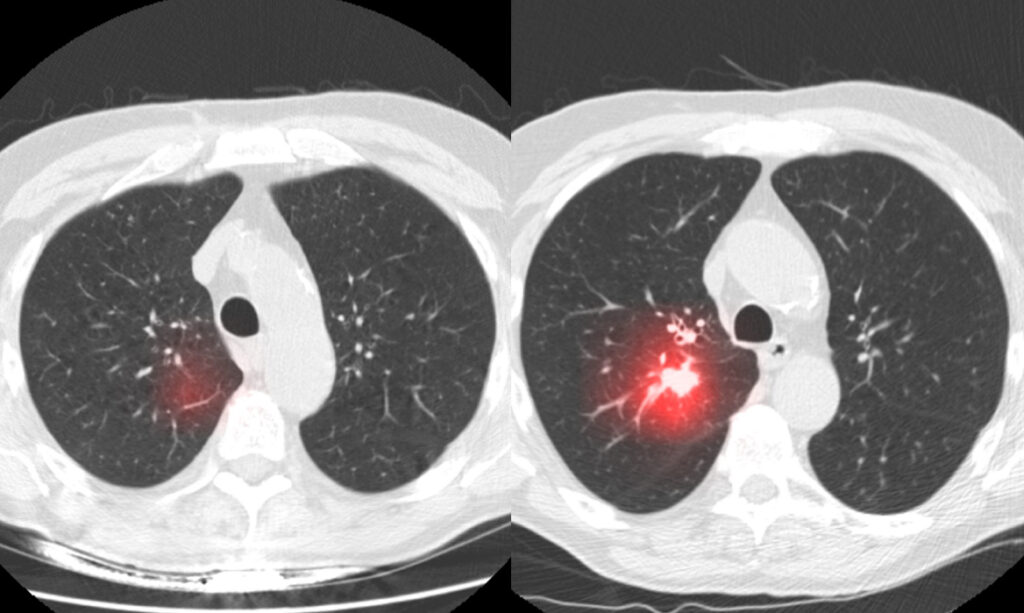

Chụp CT phổi (Computed Tomography – CT scan của phổi) là một phương pháp y khoa không gây tổn thương, không gây đau đớn. Phương pháp này thực hiện thông qua việc sử dụng tia X để tạo ra các hình ảnh chi tiết của phổi và cấu trúc xung quanh cơ quan này. Quá trình này giúp bác sĩ xác định và đánh giá các vấn đề về sức khỏe của phổi như: Bệnh phổi, nhiễm trùng phổi, khối u hoặc các tổn thương khác,…

- Hình ảnh chi tiết: CT phổi tạo ra các hình ảnh chi tiết hơn so với các phương pháp hình ảnh khác. Từ đó, có thể giúp cho việc chẩn đoán và quan sát rõ hơn các vùng bị tổn thương hoặc bất thường của bác sĩ cũng chính xác hơn.

Chụp CT phổi có khả năng phát hiện ra các vấn đề về phổi, bao gồm bệnh ung thư phổi. Tuy nhiên, khả năng phát hiện phụ thuộc vào kích thước và loại bệnh ung thư, vị trí và các yếu tố khác.